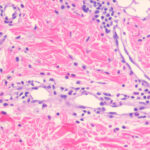

cases are said to have a small-vessel, neutrophil-rich leukocytoclastic vasculitis beneath the blister. Histologic features more routinely identified with lupus erythematosus are not present. Another histologic finding that is not emphasized in most case reports is the presence of dermal mucin and hyaluronic acid as defined by Alcian blue stain at pH 2.5 . The frequency of mucin deposition is unknown.